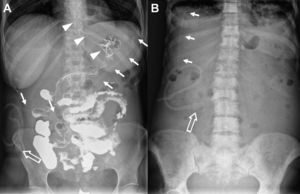

Material y métodosEl catéter tunelizado PleurX® (Denver Biomedical, Golden CO) es un catéter de silicona flexible de 15,5Fr de diámetro. Consta de un manguito de poliéster que se aloja en el tejido celular subcutáneo y que favorece la adhesión al mismo. En el extremo exterior el catéter consta de una válvula unidireccional que previene el paso de cualquier sustancia hacia la cavidad peritoneal. En el extremo interior, el catéter está fenestrado en los últimos 24cm. El catéter es fácilmente visible en estudios radiológicos (fig. 1).

A) Radiografía abdominal de la paciente número 4 donde se observa la porción intraperitoneal (flechas rectas) y externa del catéter tunelizado así como la válvula unidireccional (flecha hueca). Sonda nasogástrica (puntas de flecha). B) Radiografía abdominal de la paciente número 1 que muestra la posición intraperitoneal del catéter tunelizado (flechas rectas) y la porción externa del mismo con la válvula unidireccional (flecha hueca).